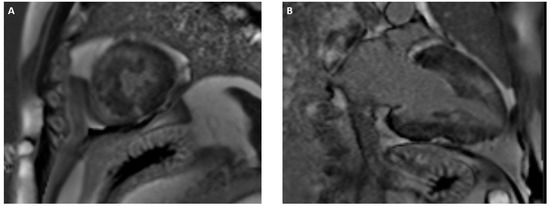

3.1. Ischemic and Non-Ischemic Dilated Cardiomyopathy (DCM)

3.2. Acute Myocarditis